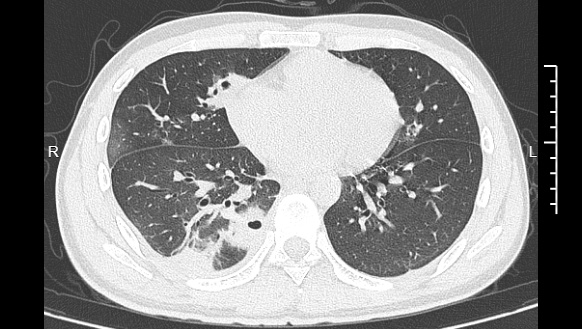

熬到第三天,小林已经烧到39℃,赶紧去医院就诊。接诊的主任医师丁群力一看他的症状,立刻安排了CT检查。结果显示:小林的肺里有十几个空洞,部分肺组织已经坏死,这是典型的血源性肺脓肿。

像小林这样,当细菌跑到肺组织上后,就会开始疯狂破坏肺细胞,引发局部炎症。随着炎症加重,肺组织会逐渐坏死、液化,最终形成一个个空洞。